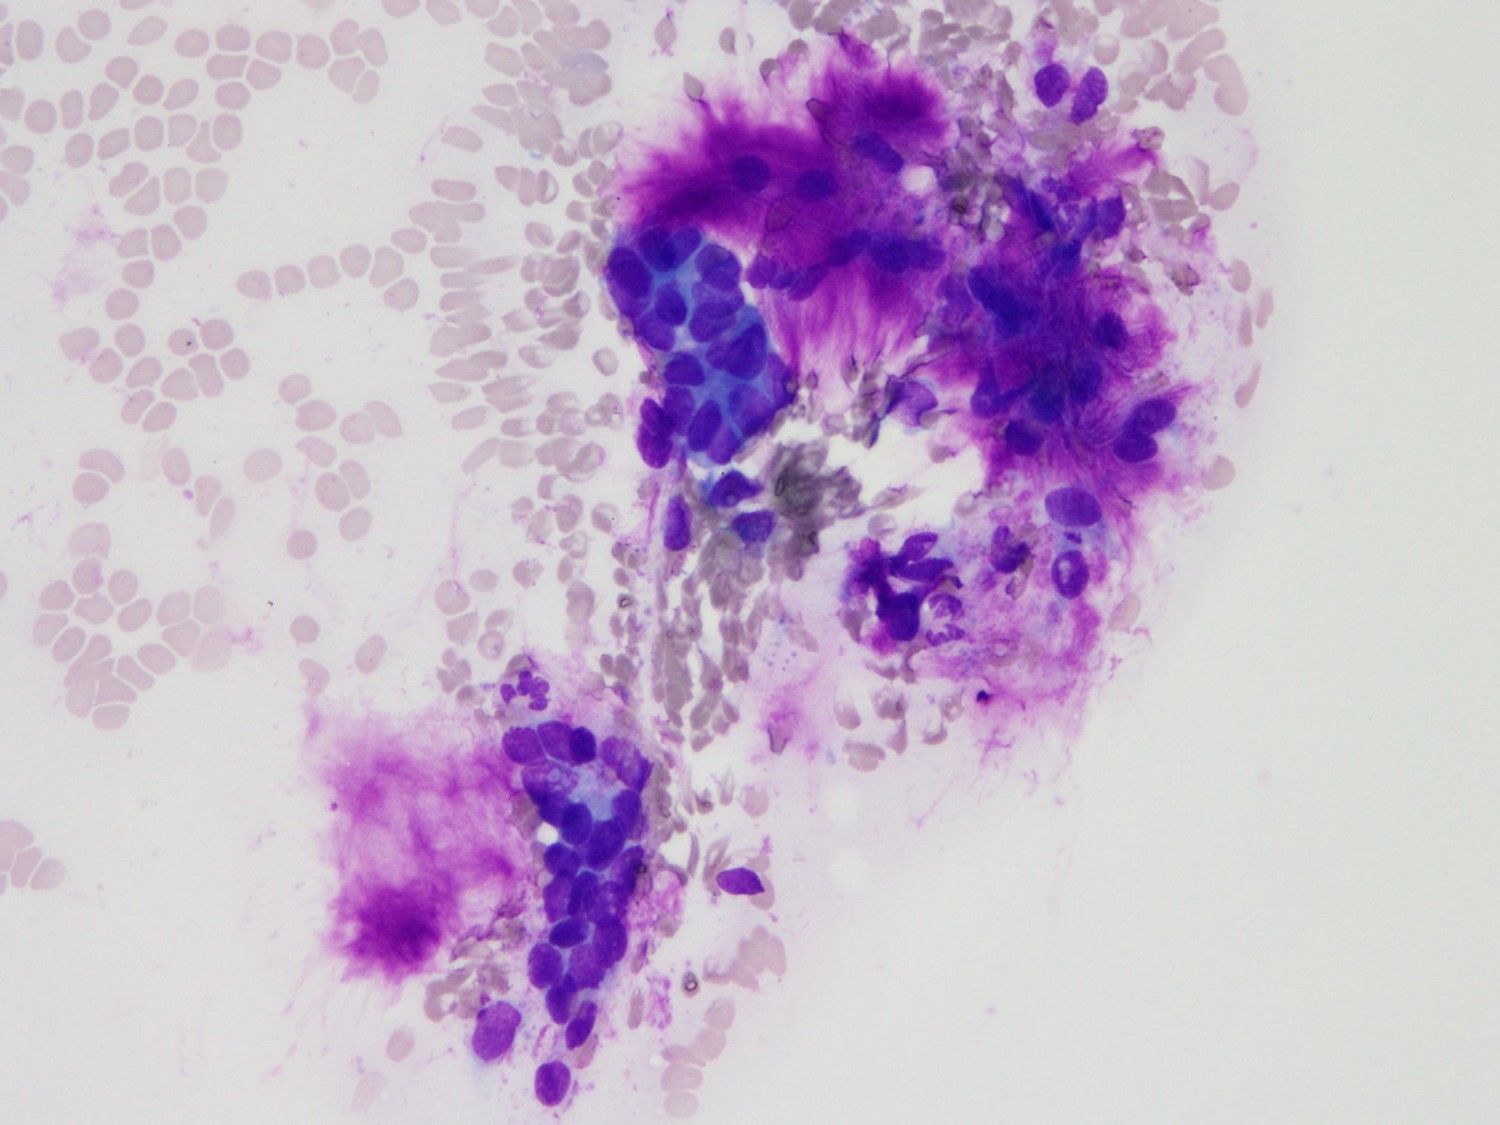

パパニコロウ染色標本では、半透明、淡紫色の粘液腫様間質を伴う、上皮細胞集塊を認めた。紡錘形核を有する筋上皮性腫瘍細胞と、シート状配列を示す腺上皮様の腫瘍細胞が見られた。メイギムザ染色標本では、異染性を示す間質性粘液が見られ、粘液の辺縁は毛羽立った様な所見を示していた。一部の細胞には核腫大・軽度クロマチン増量した細胞や、核小体明瞭な細胞の小集塊が見られたが、異型細胞少数であり、異型は弱いと判断され、まずは多形腺腫を第一に考え、陰性と判定された。